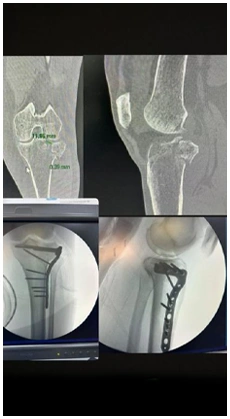

As osteotomias são procedimentos cirúrgicos que envolvem o corte e reposicionamento dos ossos ao redor da articulação do joelho para corrigir deformidades angulares, como a osteoartrose em estágio inicial ou instabilidade ligamentar. Esse procedimento visa redistribuir as forças na articulação do joelho e aliviar a pressão sobre as áreas danificadas da cartilagem.